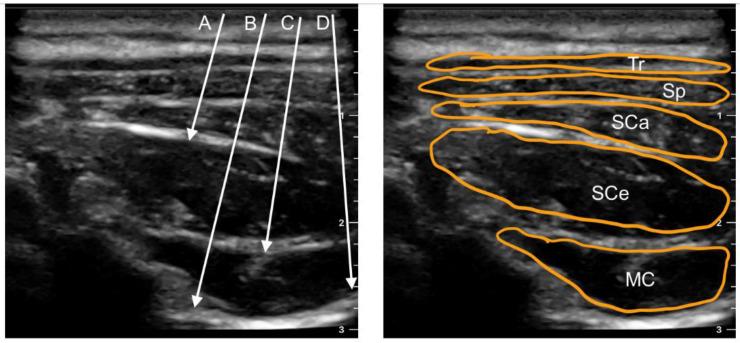

Postoperative pain is common following spine surgery, particularly complex procedures. The main anesthetic efforts are focused on applying multimodal analgesia beforehand, and regional anesthesia is a critical component of it. The purpose of this study is to examine the existing techniques for regional anesthesia in cervical spine surgery and to determine their effect and safety on pain reduction and postoperative patient's recovery. The electronic databases were searched for all literature pertaining to cervical nerve block procedures. The following peripheral, cervical nerve blocks were selected and described: paravertebral block, cervical plexus clock, paraspinal interfascial plane blocks such as multifidus cervicis, retrolaminar, inter-semispinal and interfacial, as well as erector spinae plane block and stellate ganglion block. Clinicians should choose more superficial techniques in the cervical region, as they have been shown to be comparably effective and less hazardous compared to paravertebral blocks.

脊柱手术后通常会出现术后疼痛,尤其是复杂的手术。主要的麻醉措施侧重于预先应用多模式镇痛,而区域麻醉是其中的关键组成部分。本研究旨在检查颈椎手术中现有的区域麻醉技术,并确定它们在减轻疼痛和术后患者恢复方面的效果和安全性。电子数据库中搜索了所有与颈椎神经阻滞程序相关的文献。选择并描述了以下外周和颈椎神经阻滞:椎旁阻滞、颈椎丛钟形阻滞、多裂肌颈、后层间、半棘间和筋膜间平面阻滞以及竖脊肌平面阻滞和星状神经节阻滞。临床医生应选择颈部较浅的技术,因为与椎旁阻滞相比,这些技术已被证明同样有效且危害较小。